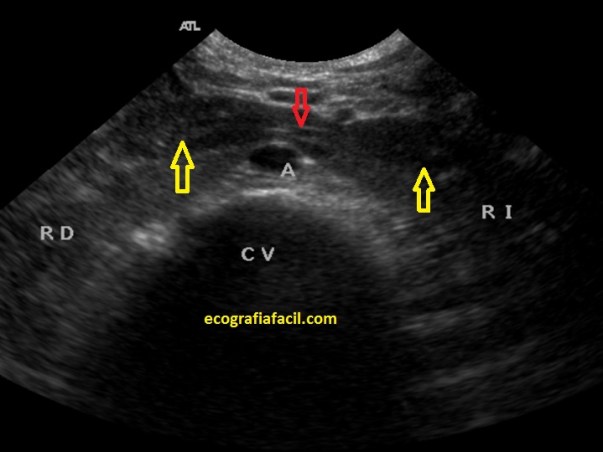

El aspecto del riñón en herradura en cuanto a su semiología es de lo más normal, pero cuando hacemos la exploración vamos a poder comprobar que el polo inferior del riñón, normalmente el derecho, porque es el que primero se explora, se orienta y continua buscando la línea media y comprobaremos como pasa por encima de Aorta, es decir, anterior a ésta y a la Cava Inferior, lógicamente.

Las flechas amarillas marcan ambos riñones y la flecha roja su unión.

Casi siempre se unen los polo inferiores de los riñones.

The aspect of the horseshoe kidney in terms of its semiology is the most normal, but when we do the exploration we will be able to verify that the lower pole of the kidney, usually the right one, because it is the one that is first explored, is oriented and continues to search the middle line and we will check how it passes over Aorta, that is, prior to this and to the Lower Cava, logically. The yellow arrows mark both kidneys and the red arrow their union. The lower poles of the kidneys are almost always joined.